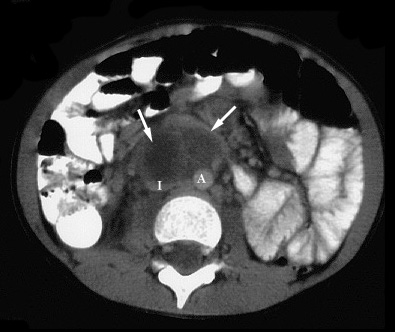

Figure 2. Axial CT image of the lower abdomen (same patient as 1.) shows a hypodense mass (arrows) with an enhancing rim anterior to the inferior vena cava (I) and aorta (A) resembling a mesenteric abscess. The inferior vena cava is compressed by the mass. |